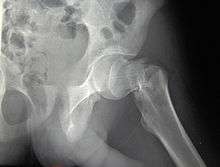

![]() AP hip radiograph demonstrating an intertrochanteric fracture | |

X-rays of the affected hip usually make the diagnosis obvious; AP (anteroposterior) and lateral views should be obtained.